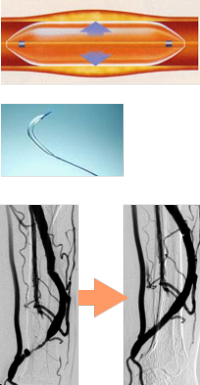

方法は狭くなった血管に風船付きのカテーテルを挿入し、風船を膨らませることで狭い血管も拡張します。その結果、血流が回復し閉塞の危険性も低下します。ただし一度狭くなった血管は再び狭くなるクセがあるため、定期的に造影および血管内治療を繰り返す必要があります。

しかし新たにシャントを作成する手術と違い入院する必要がないこと、穿刺可能な血管が短くならないことから、全国的にもシャントトラブルの解決方法として幅広く行われています。

院長は約800例の実地経験を持っており、風船による血管形成術(PTA)の他に完全閉塞例に対する血栓吸引術もクリニックで施行可能です。